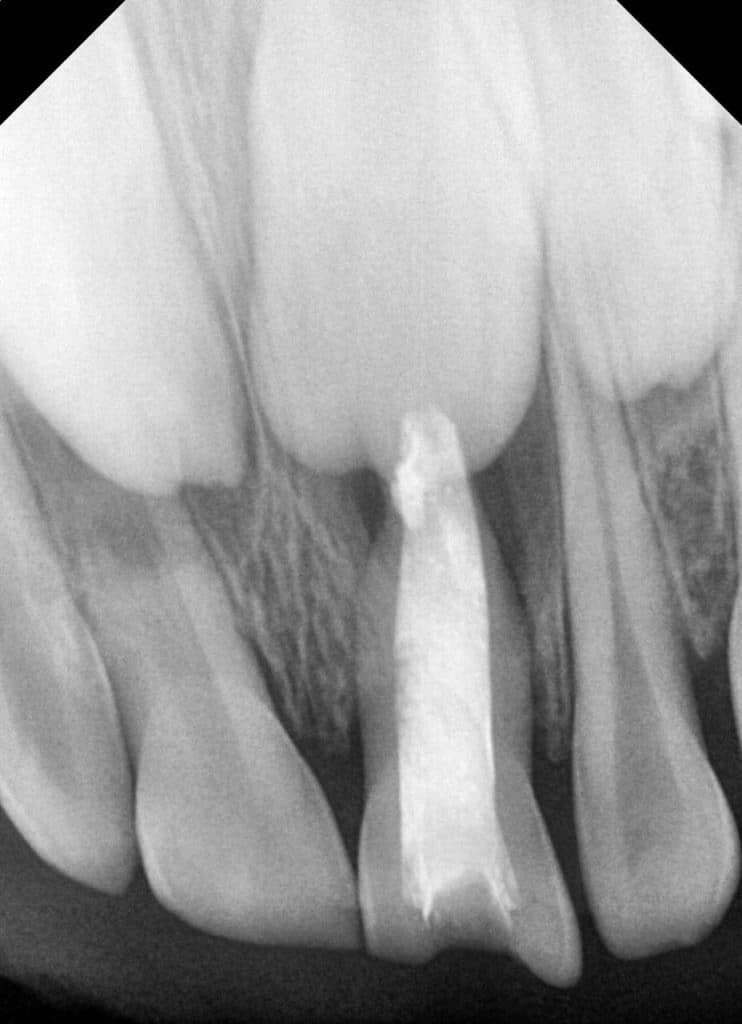

One day, a friend of mine called and told me that her 4-year-old nephew had an accident 6 months ago, and during this period the color of the tooth changed and the appearance of an abscess with pain lasted for a long time. We agreed on a day for the clinical examination, and when we examined her clinically, we found an actual change in The color of the tooth to a blackish-gray color, with pain during palpation, the presence of clear dents, and a change in the color of the gums, and when x-rays were taken, it showed (Fig 1 ).

All symptoms indicate resorting to the pulpectomy treatment plan, but while reading the x-rays, we suspected that there was a fracture at the end of the root, and this is what made us a big lake, and we had two options for treatment

Therefore, I was a fan of the first plan, and strongly, and here we have started, and the fact that the area was infected and the presence of a lesion, and this treatment plan needs irrigation so that we can empty the internal inflammatory substance in the bone because there are abrasions, and the fact that the x-rays showed me a semi-fracture inside The root was at the Apex, as I was very afraid of using sodium hydrochloride in the first visit, so the first visit was only drainage by warm Normal saline (Fig 2 ), where it is benefited from the warm Normal saline as being a very excellent agent for the exit of surgery and pus from the tissues and does not cause pressure on the tissues and causing pain During the irrigation process, in addition to being very safe, sodium hydrochloride avoids an accident if there is a root fracture.